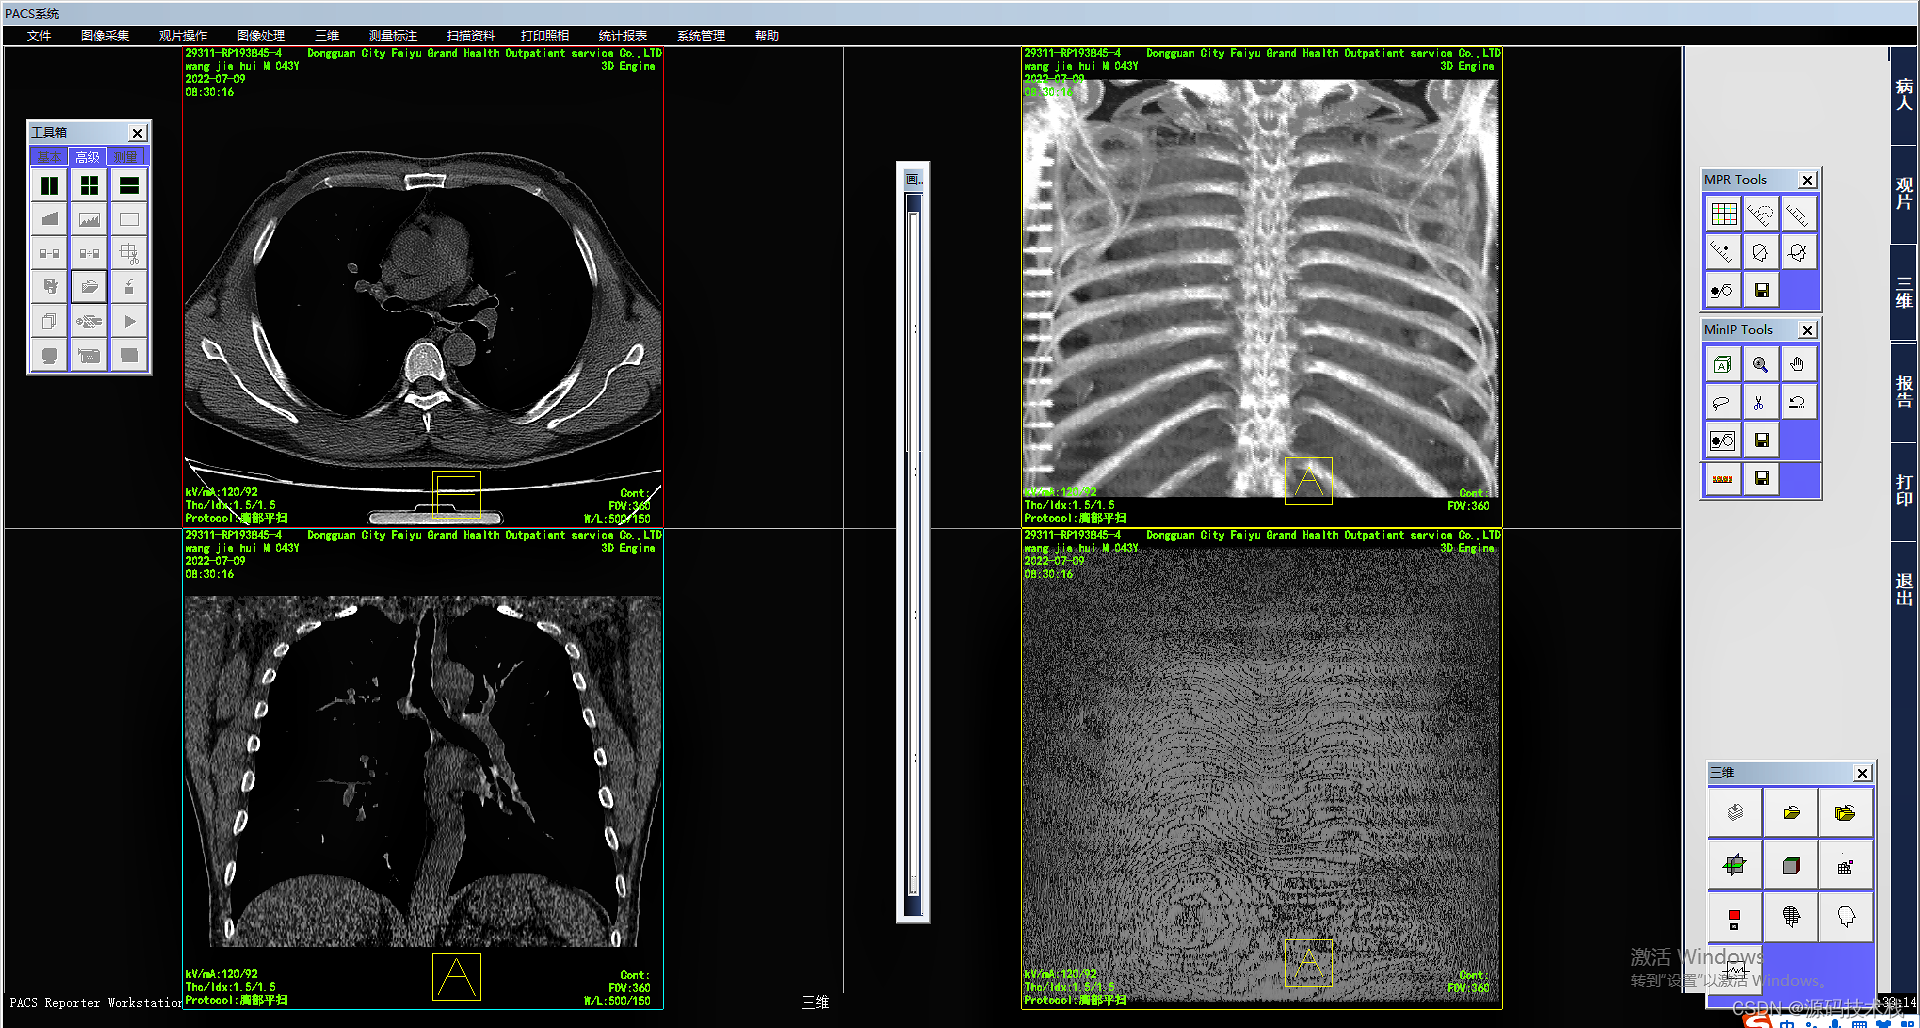

影像查阅

系统采用DICOM和非DICOM格式获取影像数据,以通讯方式采集影像原始DICOM数据;

支持多屏和竖屏显示;支持动态影像电影方式回放、逐帧漫游和冻结;

支持同屏显示多幅影像,自定义显示矩阵;

支持同屏显示同一患者在不同检查设备检查的多个动态电影图像;

支持检查模式、比较模式和打印模式的图像显示;

支持多屏显示同一患者的不同序列图像或不同患者的图像;

支持同屏分格显示患者不同体位和不同设备的影像;

支持不同患者间的影像对比。

图像后处理与重建

·MPR\CPR(三维多平面重建)

·VRT(三维容积重建)

·SSD(三维表面重建)

·VE(虚拟内窥镜)

·MIP(最大密度投影)

·MinIP(最小密度投影)

·CalSCore(心脏图像冠脉钙化积分)

影像处理和测量功能

系统支持支持窗宽、窗位预设,连续调整窗口准位和直方图,图像均衡、图像平滑处理和边缘增强;

支持对比度调节、正负像旋转、影像黑白反转、影像水平和垂直翻转、灰阶转换和任意角度旋转等;

支持滤波、锐化、播放和彩色绘制等;

支持ROI值、长度、角度和面积等数据测量与计算;

支持数字减影、无级缩放和局部放大;

支持文字和图形标记;查询和保存DICOM头信息;

支持不同影像格式转存;

支持根据检查项目自动应用相应的预设窗宽、窗位。